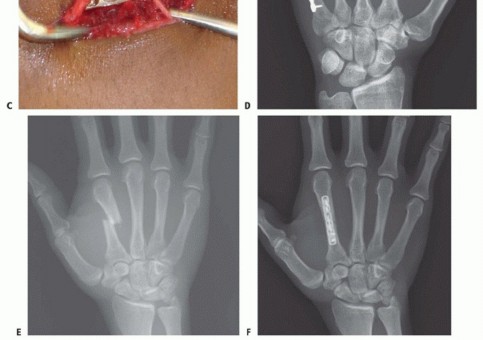

Once reduced, fixation can be achieved via crossed Kirschner wires or retrograde intramedullary pinning (the "bouquet" technique). However, the modern gold standard for minimally invasive fixation is the retrograde intramedullary headless compression screw. A small stab incision is made over the dorsal aspect of the flexed MCP joint. The entry portal is meticulously established in the articular "safe zone" of the metacarpal head—specifically the dorsal-ulnar or dorsal-radial collateral recess, strictly avoiding the central weight-bearing articular cartilage.

A guidewire is advanced down the medullary canal across the fracture site under fluoroscopic guidance. After confirming perfect rotational alignment and length, the canal is sequentially broached or drilled, and an appropriately sized headless compression screw is buried beneath the articular cartilage. This technique provides robust, load-sharing stability that allows for immediate, unrestricted active range of motion, vastly reducing the incidence of postoperative stiffness compared to traditional K-wire constructs.

When closed reduction fails, or for complex, comminuted, or multiple metacarpal fractures, Open Reduction and Internal Fixation (ORIF) is mandated. A dorsal longitudinal or slightly gently curved incision is made centered over the fractured metacarpal. Careful subcutaneous dissection is performed to identify and meticulously retract the dorsal sensory nerve branches using vessel loops. The extensor apparatus is exposed. Depending on the fracture location, the extensor tendon can be retracted laterally, or the extensor mechanism can be split longitudinally (e.g., splitting the EDC tendon) to access the dorsal periosteum.

Periosteal elevation must be judicious and strictly limited to the footprint required for plate application. Circumferential stripping of the periosteum is a catastrophic error that devascularizes the bone fragments and invites nonunion. The fracture site is gently debrided of hematoma and interposed soft tissue. Anatomical reduction is achieved using specialized reduction forceps, taking immense care to avoid crushing fragile cortical edges. Provisional fixation is maintained with fine (0.035-inch or 0.045-inch) K-wires.

When a dorsal plate is required, it must be meticulously contoured to match the natural dorsal convexity of the metacarpal to prevent secondary displacement during screw insertion. For transverse fractures, the plate is applied in compression mode using eccentrically placed screws. For comminuted fractures, the plate functions as a bridge, bypassing the zone of comminution to maintain length and alignment without disturbing the fracture hematoma. Locking screws are utilized in osteoporotic bone or very short distal segments to prevent hardware pullout.

Following definitive fixation, a rigorous fluoroscopic check is performed in multiple planes to confirm anatomical reduction, appropriate hardware placement, and crucially, to ensure no screws are penetrating the volar cortex excessively, which could tether the underlying flexor tendons. The tourniquet is deflated, meticulous hemostasis is achieved, and the extensor mechanism is meticulously repaired with fine absorbable sutures. The skin is closed without tension, and a bulky, well-padded dressing is applied, splinting the hand in the intrinsic-plus position.

Clinical & Radiographic Imaging Archive